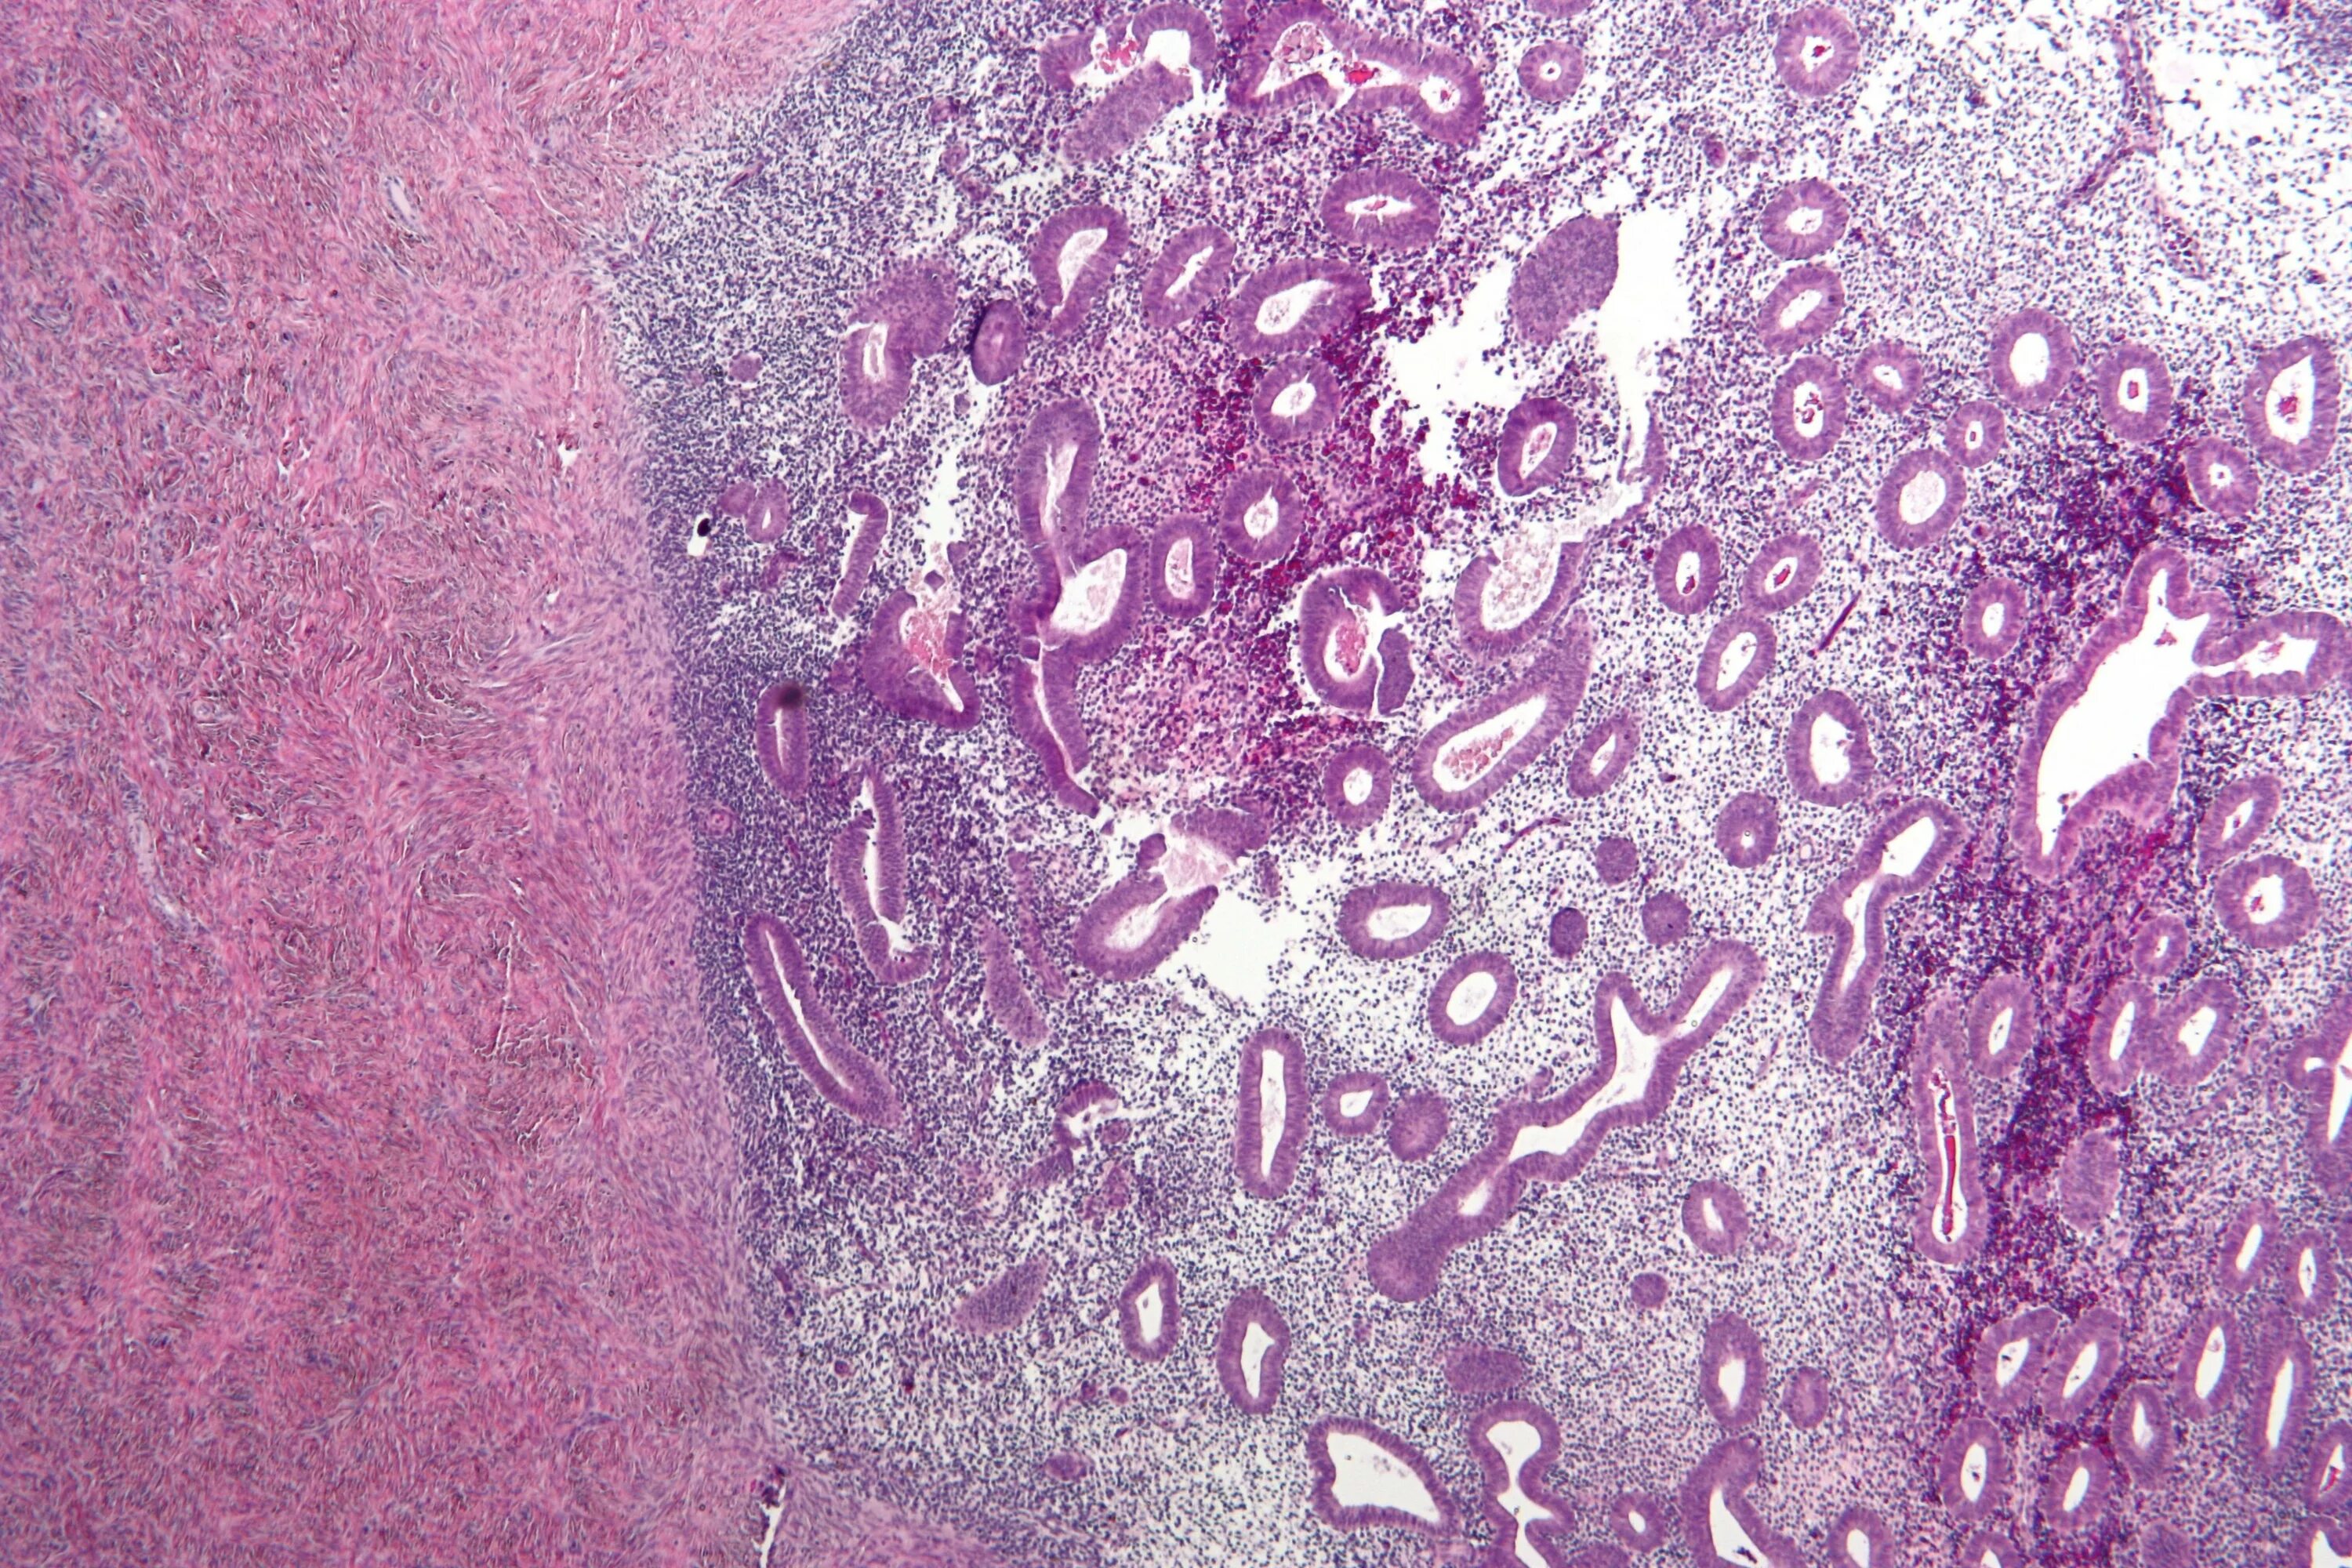

Эндометрит гистология